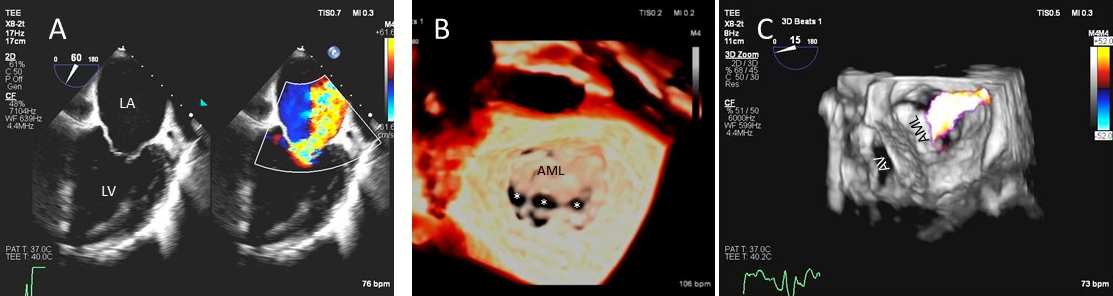

Besides prolapsing or flail scallops, MR jet may also originate between individual scallops. This occurs more commonly between the posterior leaflet through cleft like indentations that sometimes extend to the mitral annulus. This origin of MR can be very difficult to diagnose on 2D TTE or TEE (Fig. 2A–C). 3D color Doppler further assists in confirming jet origin at the site of suspected leaflet pathology/ies including presence of mitral valve cleft like indentation/s. Presence of calcification on the annulus and leaflets and in the subvalvular apparatus further assists surgeon in planning repair [21]. Visualization of the valve from the LV perspective adds further information on leaflet morphology, coaptation and regurgitant site/s particularly if jet originates from mitral valve clefts. Optimal visualization of the MR jets using real-time 3D TEE leads direct guidance for catheter movement and positioning of the implanted device(s) capturing the opposing sides of anterior and posterior mitral leaflet scallops during catheter based MV interventional procedures [22].

Fig. 2.Mitral leaflet Cleft. (A) TTE short axis at the mitral valve level showing posterior mitral cleft. (B, C) Isolated cleft within the P2 segment of the posterior leaflet (associated with mitral regurgitation) on 3D TEE and TTE short axis views. AML, anterior mitral leaflet; PML, posterior mitral leaflet.